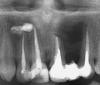

iren123 Опубликовано 3 февраля, 2010 Поделиться Опубликовано 3 февраля, 2010 Пожалуйста проконсультируйте мою ситуацию. Около 10 лет назад была сделана операция по удалению кисты больших размеров, и почемуто с удалением абсолютно здоровго зуба, который ему попросту мешал. Причиной был 1 зуб с левой стороны. В течение некоторого времени врач закладывал в дыру марлевую турунду и менял периодически. Дальше в какойто момент он сказал что все номально и сказал что лечение больше не нужно, при этом дырку эту совсем не зашивал. визуально было заметно, что это дыра в кости зарастает, но спустя время пошел гной из дыры. Обратилась к другим врачам, выяснилось, что там была оставлена эта турунда и она вросла в кость и началась новое разрушение кости. Была снова сделана чистка этой кисты, потом несколько недель мне вытаскивали ниточки которые все время появлялись, кость нарастала рубцеванием, потом зашили и как то все успокоилось. Осталась только как бы маленькая дырочка сверху над зубом, чтото вроде шрама. Сейчас она увеличилась, я так понимаю это свищ, снова оттуда начали лезть те самые ниточки. В прошлом году мне их вытащили, снимок сделанный тогда ничего не показал. На данный момент из этой дырочки еще и гной проступает и по утрам идет достаточно болезненный отек той стороны лица где все это происходит.Врач сказал, там скорее всего хронический остеомиелит. Нужно удаление кисты, а потом наращивание кости, но есть вероятность того что это может привести к осложнениям, если там внутри гнойная киста.Последний снимок прилагаю. Ссылка на комментарий